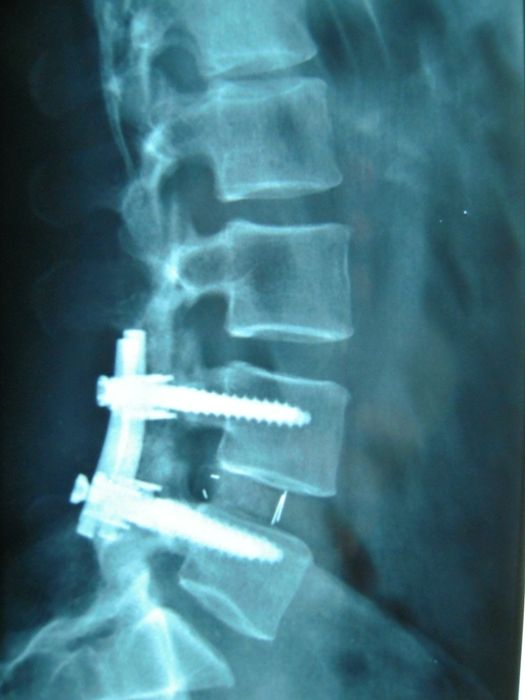

Campi d’interesse: chirurgia vertebrale degenerativa e deformativa (ernie del disco, stenosi del canale vertebrale, spondilosi, spondilodiscoartrosi, imbalance spinale e instabilità vertebrali) con tecniche open, mini-invasive o percunee. Patologie intracraniche (meningiomi, gliomi, neurinomi, e conflitti neurovascolari) e disturbi della cinetica liquorale (idrocefalo normoteso e idrocefalo da stenosi dell’acquedotto di Silvio).